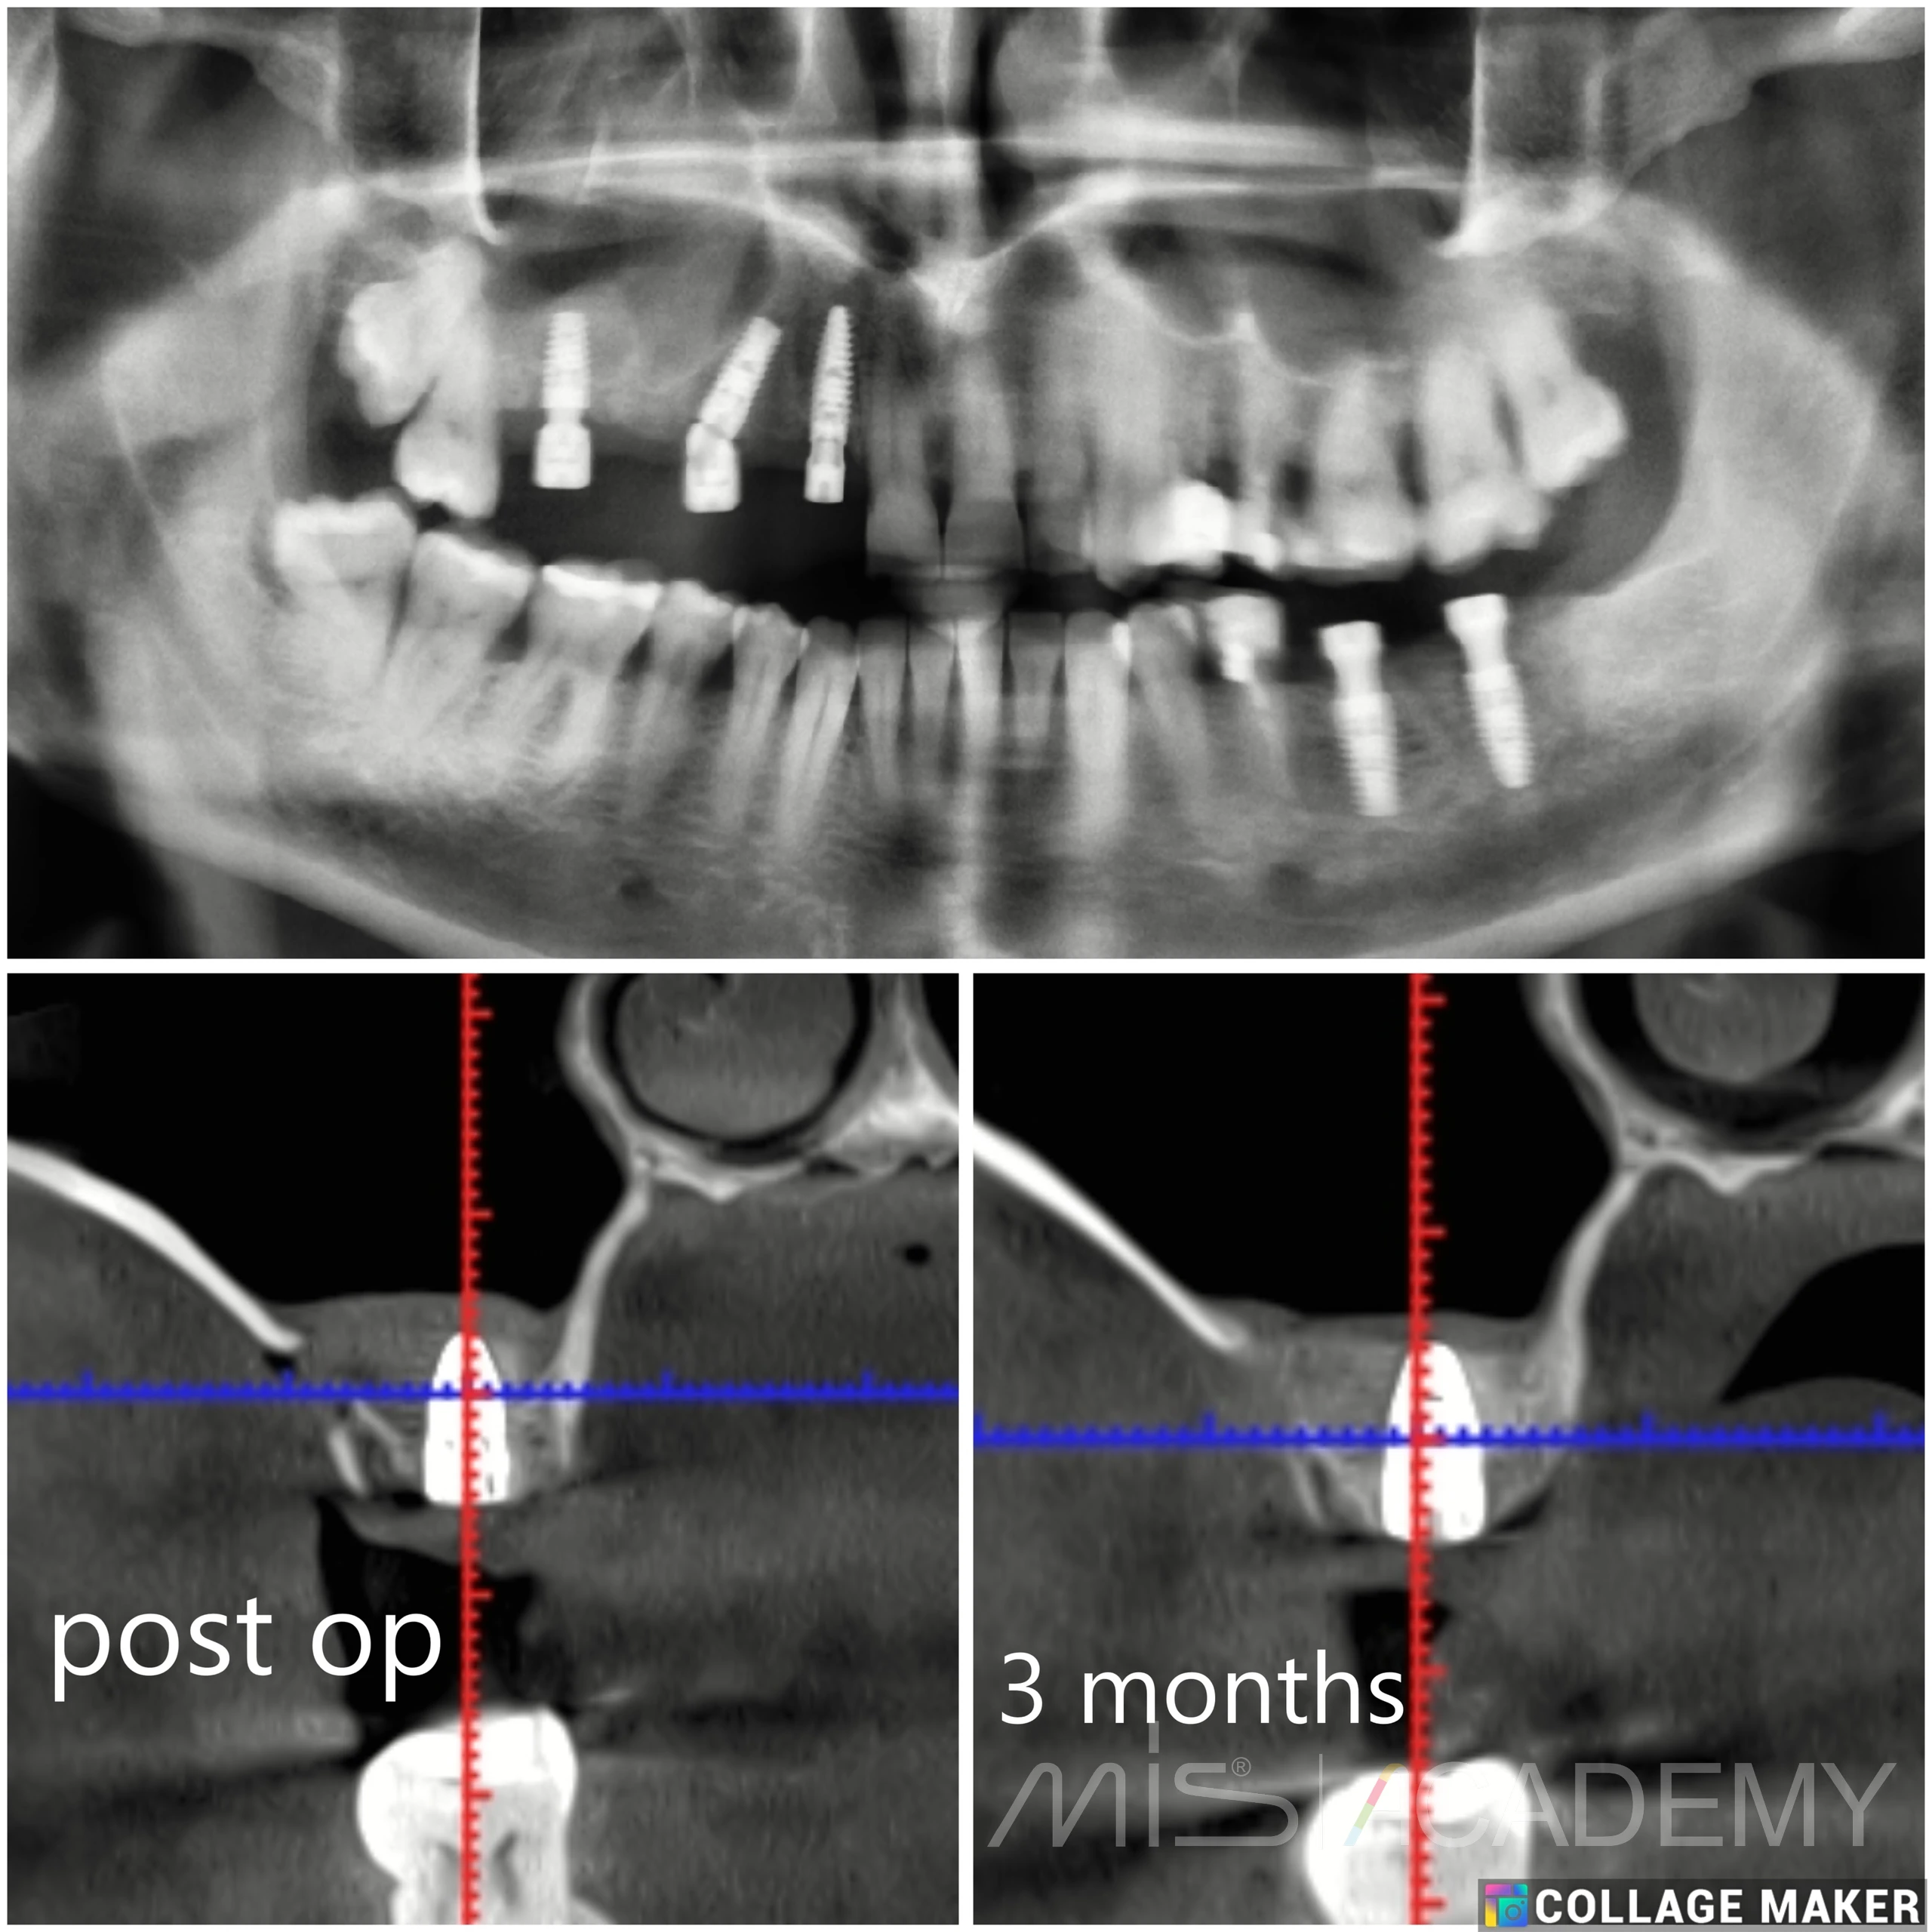

На верхней челюсти установлены три имплантата MIS C1

— Первый имплантат установлен под наклоном в обход гайморовой пазухи (free-hands), использован угловой multi unit.

— Второй — в прямой проекции с использованием connect.

— Третий имплантат установлен по методике TENT: отслаивание гайморовой пазухи, укладывание губки «Колапол» и PRF, установка имплантата, закрытие хирургического окна мембранной из PRF.

— Через 3 месяца произведен разрез в области третьего имплантата, установка прямого multi unit.

P/S. Получили кость 400 HU.